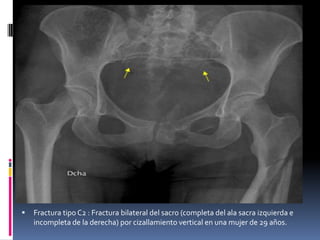

Grupo C-2

disrupción completa en hueso iliaco: C-21, articulación sacroiliaca: C-2-2 ó hueso sacro C-2-3.

Fractura tipo C2 : Fractura bilateral del sacro (completa del ala sacra izquierda e

incompleta de la derecha) por cizallamiento vertical en una mujer de 29 años.

Grupo C-2 Fracturas concompromiso unilateral completo y contralateral incompleto del anillo posterior. Se diferencian según la ubicación del rasgo con disrupción completa en hueso iliaco: C-21, articulación sacroiliaca: C-2-2 ó hueso sacro C-2-3.

 Fractura tipo C2: Fractura bilateral del sacro (completa del ala sacra izquierda e incompleta de la derecha) por cizallamiento vertical en una mujer de 29 años.